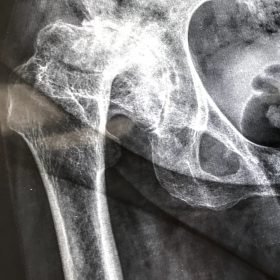

Διάγνωση- Σταδιοποίηση

Διακρίνονται σε 4 στάδια.

Στάδιο Ι. Στένωση του μεσαθριου διαστήματος

Στάδιο ΙΙ. Σκλήρυνση του υποκύμενου χόνδρου

Στάδιο ΙΙΙ. Σκλήρυνση του υπερκείμενου χόνδρου, καταστροφή του υποχόνδρινου οστούν, σχηματισμός οστεόφυτων, οίδημα αρθρώσεως και βραδυνός πόνος

Στάδιο IV. Οστική καθίζηση, καταστροφή μαλακών μορίων μυϊκών ομάδων, υπεξάρθρημα της αρθρώσεως και αλλαγή του μηχανικού άξονα